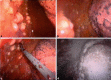

Malignant pleural mesothelioma is a rare malignant disease that in the majority of cases is associated with asbestos exposure. The incidence in Europe is about 20 per million inhabitants and it is increasing worldwide. Initial symptoms are shortness of breath, pleural effusion, cough, and chest pain. The typical growth pattern is along the pleural surface; however, infiltration of the lung and/or mediastinal and chest wall structures can occur in a more advanced stage. Ultimately, distant metastases outside the chest can result. Several histological subtypes of pleural mesothelioma exist, which must be differentiated from either benign diseases or metastases in the pleural space by other tumor entities. This differential diagnosis can be very difficult and a large panel of immunohistochemical markers is required to establish the exact diagnosis. The standard procedure for confirming the disease and obtaining sufficient tissue for the diagnosis is videothoracoscopy. Full thickness biopsies are required, while transthoracic needle puncture of pleural fluid or tissue is considered to be insufficient for a cytological diagnosis. Complete and detailed staging is mandatory for categorization of the disease as well as for therapeutic decision making.